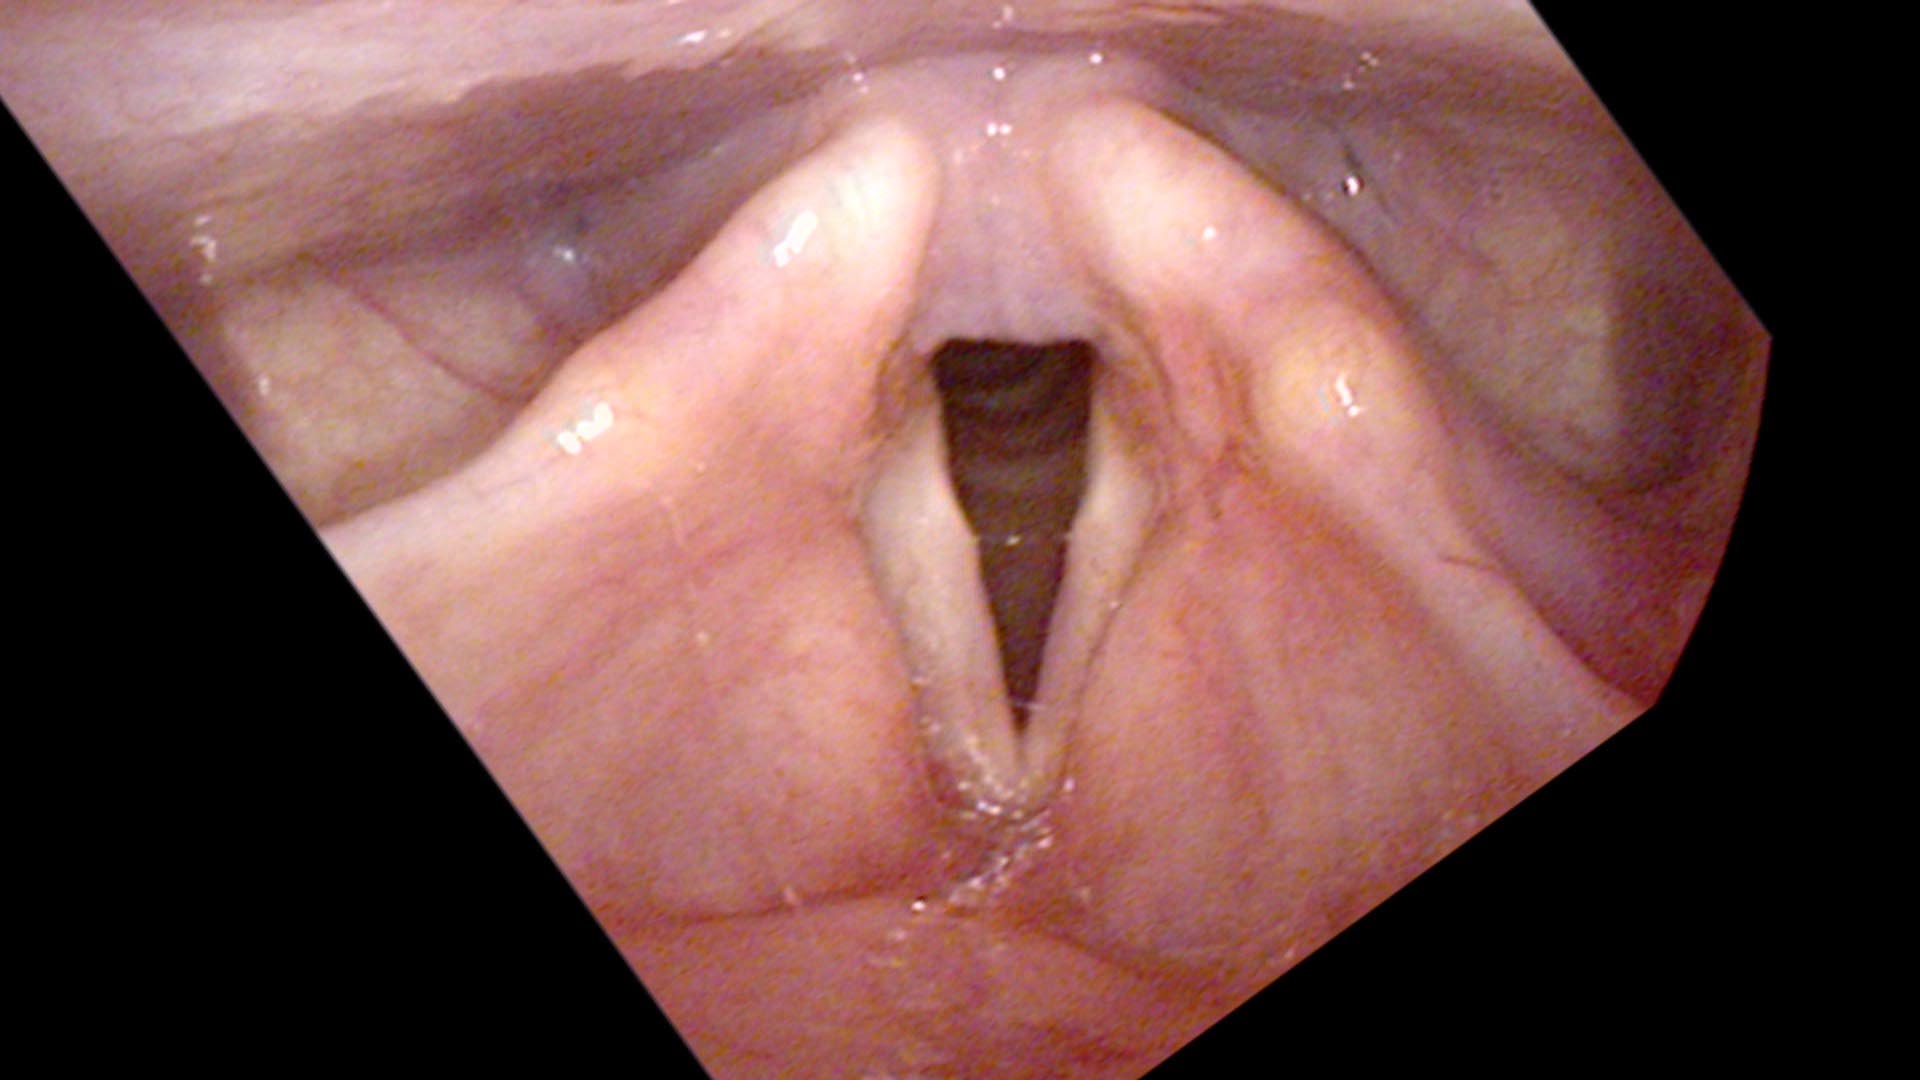

On vocal capabilities testing, her speaking pitch is lower than average for a woman her age. The swelling test reveals an onset delay on a specific note, consistent on repeated trials. On endoscopy, there is a bilateral swelling in the center of her vocal cords with a small air leak behind them. Two vocal cord swellings from overuse. Her lesson plan has been her downfall — or rather, her love of teaching has been.